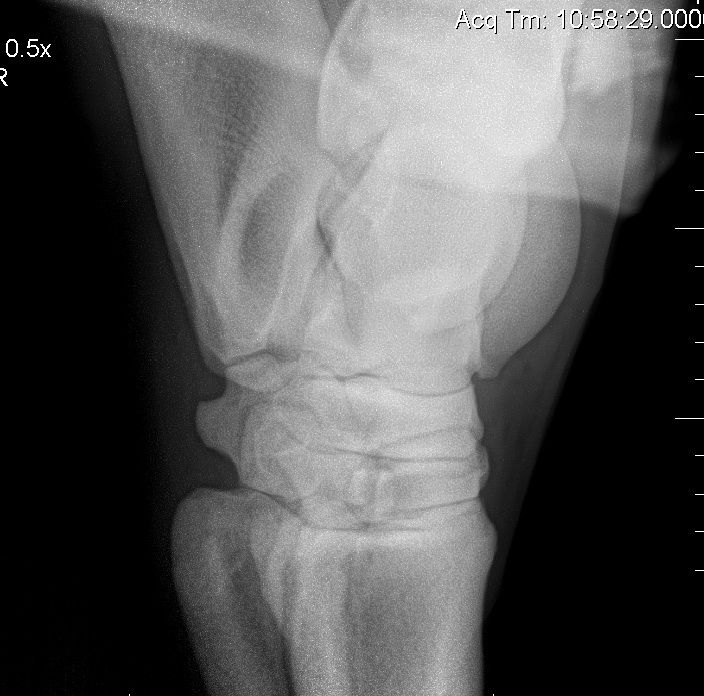

Déconnecté | Je viens enfin de récupérer les 3ième radios de mon cheval qui souffre d'un éparvin Le véto m'a montré ou c'était (j'ai fais des ronds pour vous montrer) mais apparement, il n'y aurait pas que ce que je montre dans le cercle, l'éparvin se voit aussi à un autre endroit. Quelqu'un sait me le dire ? Première radio à 4 ans [url=https://www.1cheval.com/membre/services/photos/images/137389.jpg] ![]() [/url] deuxième radio en avril 2012 [url=https://www.1cheval.com/membre/services/photos/images/137390.jpg] ![]() [/url] Et troisième radio fin septembre qui montre une évolution postive (éparvin en cours de solidification après avoir reçu du Tildren en juin) [url=https://www.1cheval.com/membre/services/photos/images/145646.jpg] ![]() [/url] Je crois qu'il y a une histoire de tassement des étages osseux ? On le voit bien sur la troisième radio... Bref aux profs des radios pouvant m'éclairer encore et encore ! Merci |

| Dire merci | L'éparvin entraine le tassement des tarses, forcément. |